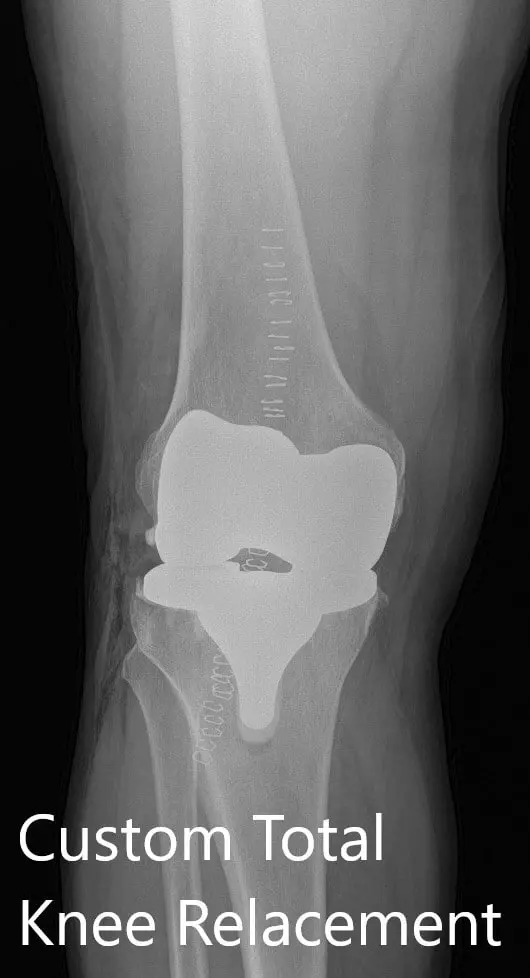

Postoperative X-ray showing AP and lateral views of the right knee

Postoperative X-ray showing AP and lateral views of the right knee - img 2